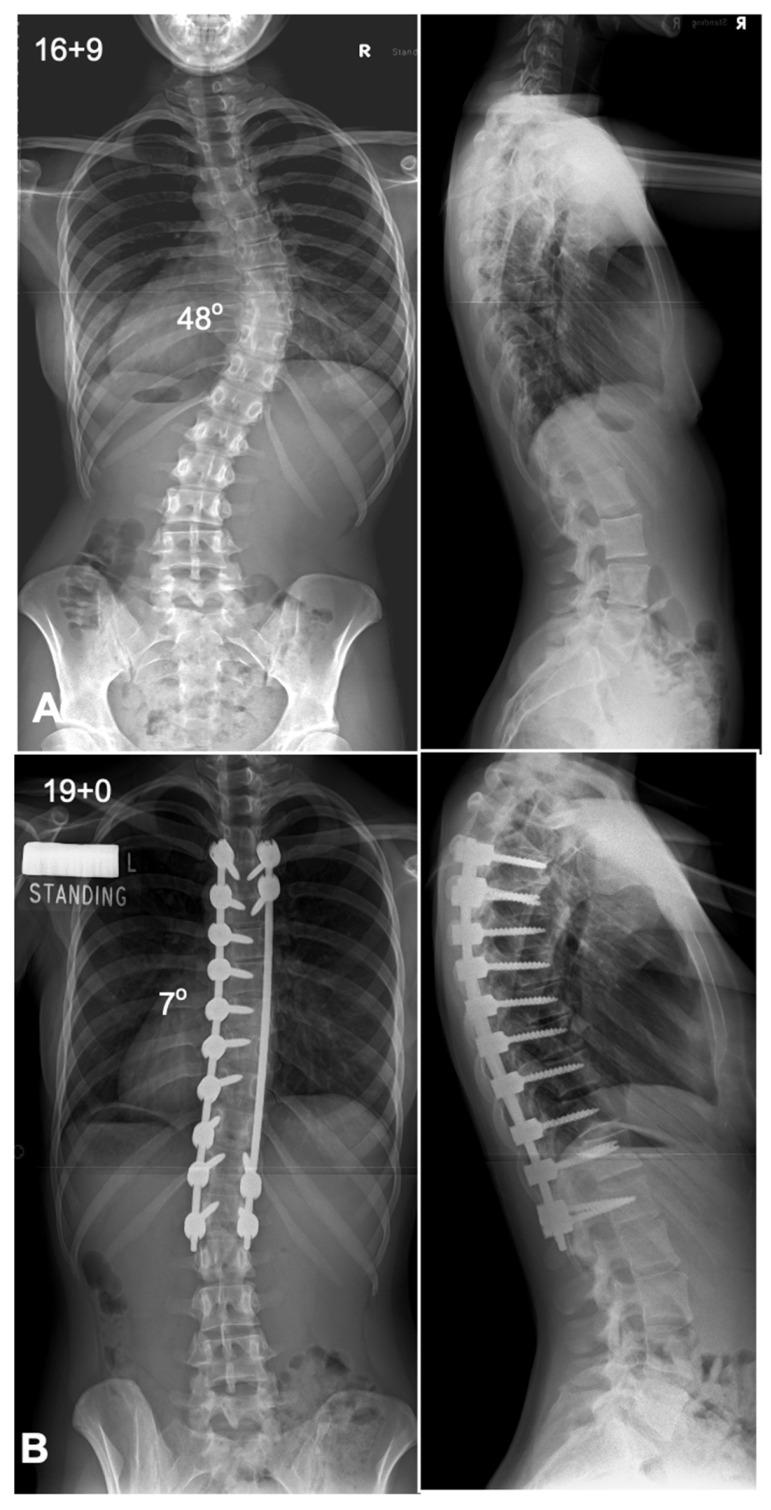

Surgical management of adolescent idiopathic scoliosis [AIS] is a complex undertaking with the primary goals to correct the deformity, maintain sagittal balance, preserve pulmonary function, maximize postoperative function, and improve or at least not harm the function of the lumbar spine. The evolution of surgical techniques for AIS has been remarkable, transitioning from rudimentary methods of spinal correction to highly refined, biomechanically sound procedures. Modern techniques incorporate advanced three-dimensional correction strategies, often leveraging pedicle screw constructs, which provide superior rotational control of the vertebral column. A number of surgical techniques have been described in the literature, each having its own pros and cons. This narrative review provides a detailed analysis of the contemporary surgical techniques used in the treatment of patients with AIS.

青少年特发性脊柱侧凸(AIS)的外科治疗是一项复杂的工作,主要目标是矫正畸形、维持矢状面平衡、保留肺功能、使术后功能最大化,以及改善或至少不损害腰椎功能。AIS外科技术的发展十分显著,已从基本的脊柱矫正方法转变为高度精细、生物力学合理的手术。现代技术采用先进的三维矫正策略,常利用椎弓根螺钉结构,从而对脊柱提供更好的旋转控制。文献中描述了多种外科技术,每种技术都有其优缺点。本叙述性综述对治疗AIS患者时使用的当代外科技术进行了详细分析。